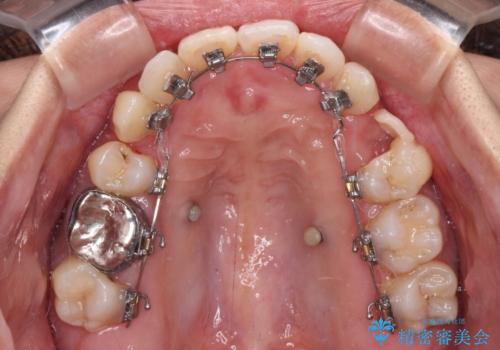

- ハーフリンガル

目立たない装置を希望されたので、上顎が裏側装置のハーフリンガルを選択し、上下左右の小臼歯(計4歯)を抜歯して矯正治療を行うこととしました。

補助装置を併用することで、八重歯を速やかに改善し、治療期間の短縮を図ることとしました。

裏側装置での矯正治療は、上顎前歯の正中のズレをまっすぐに改善することが難しいのですが、きれいに整えることができました。

補助装置を用いて抜歯したスペースを速やかに閉じたことで、短期間での治療となりました。